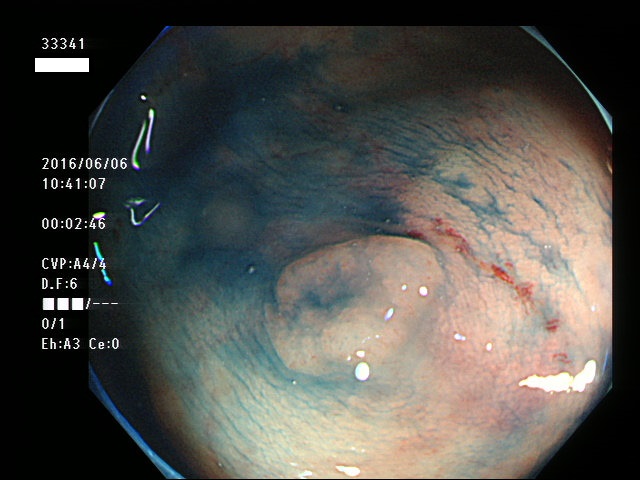

上記100名より抽出した平坦・陥凹型腺腫(=癌化の危険が高いが見落としやすい病変)の内視鏡写真

33300 33301(SSA/Pのみ) 33304 33306 33308 33311 33312(SSA/Pのみ) 33315 33319 33320 33321 33323 33324 33326 33327 33329 33330 33334 33338 33340 33341 33342 33345 33346 33350 33351 33355 33360 33361 33362(SSA/Pのみ) 33363 33366 33368 33372 33373(SSA/Pのみ) 33376 33377 33379 33382 33385 33386 33389 33392 33393 33394 33395 33396

33398 ・・・・・・の48名